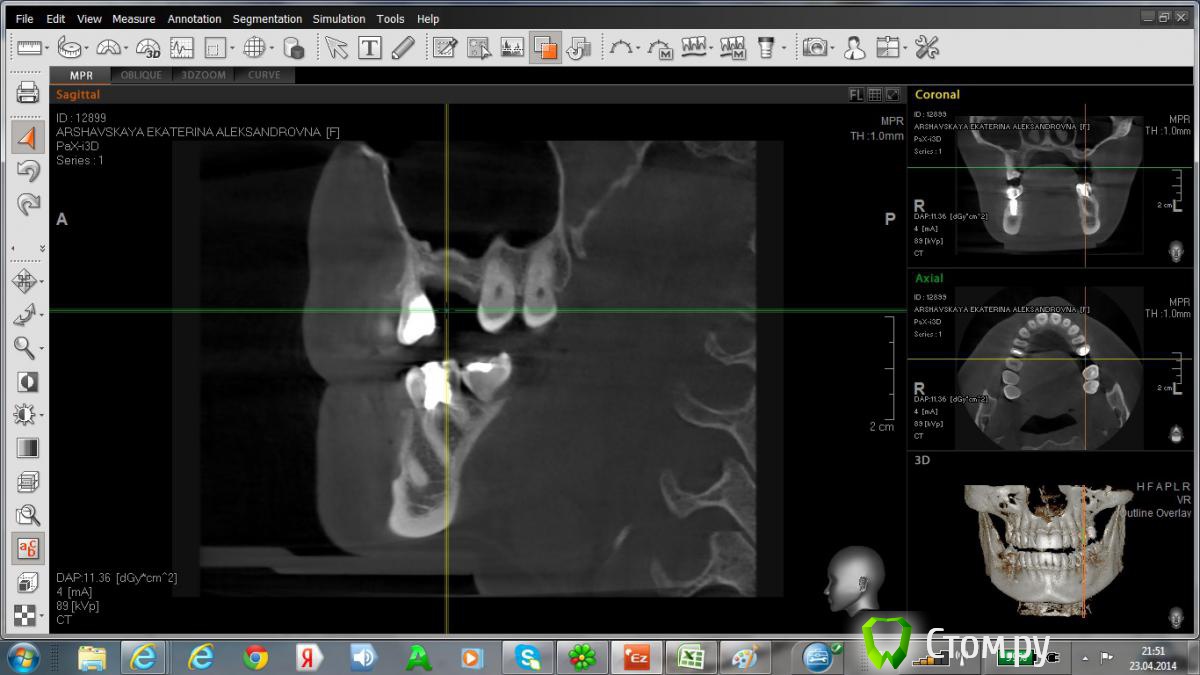

Катриниум Опубликовано 22 апреля, 2014 Поделиться Опубликовано 22 апреля, 2014 Добрый день! Прошу проконсультировать по имплантации в область 5,6 зуба (сверху слева). Возможно ли в моем случае одномоментная имплантация с синусом , после удаления 5 зуба. Сколько по времени придется ходить без зубов, и насколько в моем случае будет травматичным синус-лифтинг. С десной в этой области тоже имеются проблемы, после неоднократного перешивания, натянута практически с щеки.Эстетический результат для меня очень важен.Посмотрите еще пожалуйста имплант в районе 6 снизу справа, ставился 1,5года назад, как он поживает?) http://www.fayloobmennik.net/3747200 Ссылка на комментарий

Катриниум Опубликовано 23 апреля, 2014 Автор Поделиться Опубликовано 23 апреля, 2014 Так видно что-то? Не знаю как правильно выбрать нужную область Ссылка на комментарий

Катриниум Опубликовано 23 апреля, 2014 Автор Поделиться Опубликовано 23 апреля, 2014 Интересующая область Ссылка на комментарий

red_butler Опубликовано 23 апреля, 2014 Поделиться Опубликовано 23 апреля, 2014 (изменено) Так видно что-то? Не знаю как правильно выбрать нужную областьУстановить крестик на пятый зуб и повернуть вдоль зубного ряда, но похоже что можно сделать одномоментно. Можно сделать временный протез, операция малотравматичная Изменено 23 апреля, 2014 пользователем red_butler Ссылка на комментарий

Bier Опубликовано 23 апреля, 2014 Поделиться Опубликовано 23 апреля, 2014 судя по костному рисунку с розовой эстетикой будут сложности. А синус и имплантат поставить - проблем не будет. Ссылка на комментарий

Mane Опубликовано 23 апреля, 2014 Поделиться Опубликовано 23 апреля, 2014 Чтоб было красиво - работа с десной в несколько этапов. Фото конечно же облегчило б ситуациюПровести синус лифтинг и имплантацию одновременно будет правильно и надежно Ссылка на комментарий